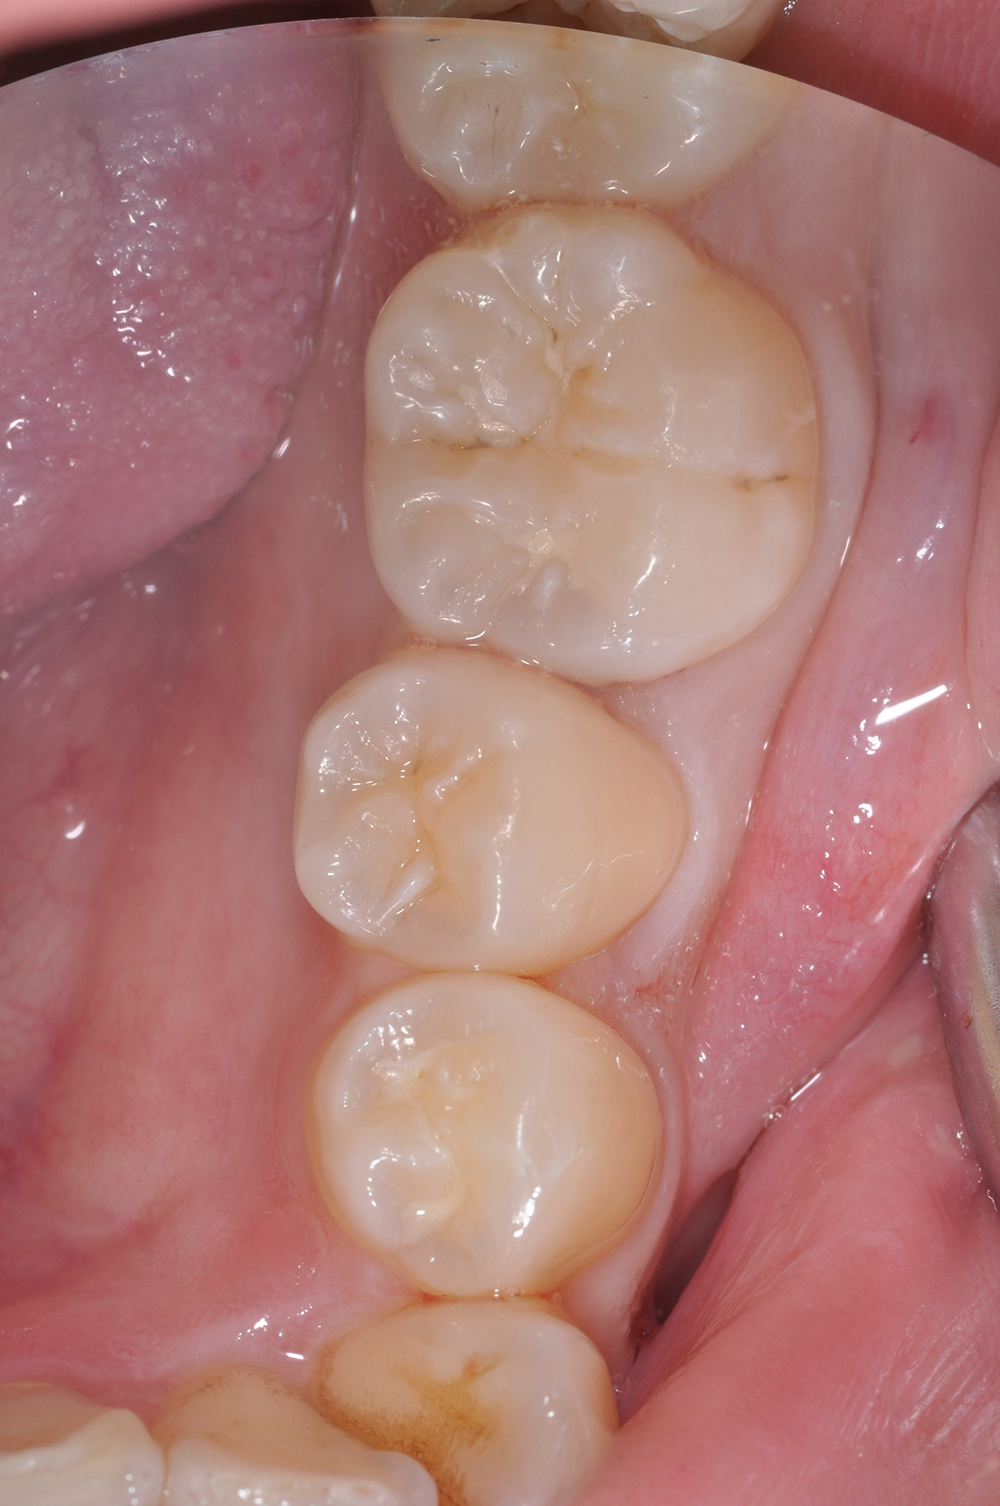

術前

術後

世代・性別

30代女性

主訴

歯がしみる時がある

治療内容

セラミックインレー

治療期間

2回

治療費

66,000円(税込)

治療のリスク

強い咬合力や衝撃によって、欠けたり割れたりすることがある